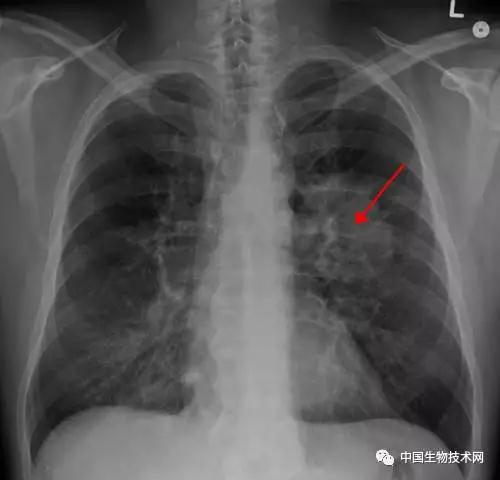

Credit:James Heilman,MD/Wikipedia

圖像來(lái)源:論文